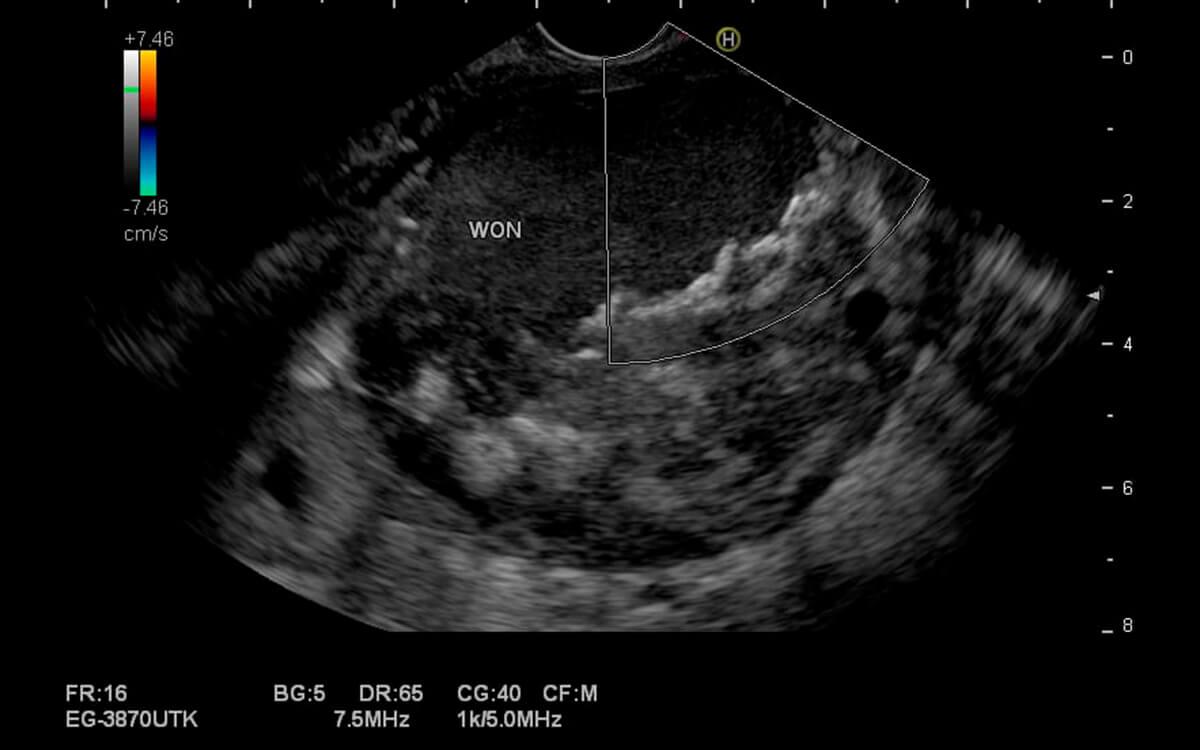

A Eco Endoscopia , é um exame diagnóstico e potencialmente terapêutico do trato digestivo alto e baixo. O médico endoscopista pode analisar o esôfago, estômago, duodeno, pâncreas, vias biliares, vesícula biliar, fígado, intestino (cólon) e reto com um ultrassom, através de acesso por endoscopia (ecoendoscopia alta) ou colonoscopia (ecoendoscopia baixa).

O Dr. Hugo Guedes, médico especialista em Eco Endoscopia pela USP e do Hospital Sírio Libanês, explica que "a ecoendoscopia possibilita examinar camadas mais profundas dos órgãos digestivos, que não poderiam ser avaliadas apenas pela endoscopia comum, pois esta permite apenas a visualização superficial de suas paredes internas".

Eco Endoscopia faz o exame ultrassonográfico do aparelho digestivo, além de permitir a realização de punção por agulha diretamente desses órgãos (ecoendoscopia com biópsia). Dessa forma, podemos analisar diversas doenças do trato digestivo, como: